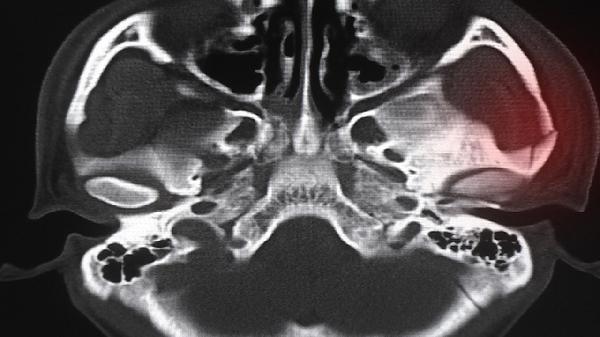

牙齿骨骼突出可以通过正畸治疗或手术矫正,具体方案需根据个人情况由专业医生评估。矫正之路是否可行,取决于骨骼突出的程度、年龄、牙齿状态等多方面因素。医生会通过影像检查、模型分析等手段制定个性化方案。

对于严重骨骼突出,单纯正畸治疗效果有限,需结合正颌手术。手术通过截骨、移位、固定等方式调整颌骨位置,改善面部轮廓。常见术式包括上颌LeFort截骨术、下颌矢状劈开术等。手术风险较高,需严格术前评估,术后配合正畸治疗以达到最佳效果。